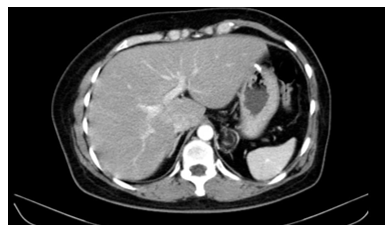

Cắt lớp vi tính ổ bụng sau mổ: Vị trí miệng nối bờ cong lớn dạ dày: không thấy dày thành, không thâm nhiễm mỡ và hạch nghi ngờ.

Hình 7. Hình ảnh dạ dày sau phẫu thuật